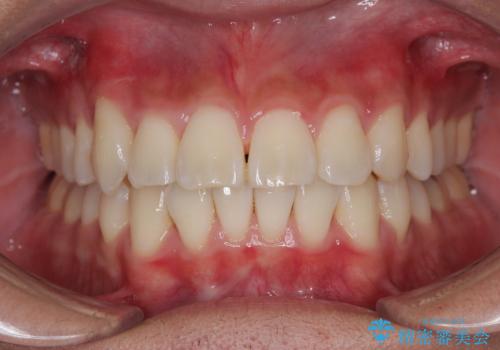

口元が突出する仕上がりとならないように、舌突出癖改善のトレーニングをしっかりと行っていただきながら、矯正治療を進めていくこととしました。

1年強でワイヤー装置を外すことができ、思ったよりも短期間で終了したため、患者様には大変喜んでいただきました。